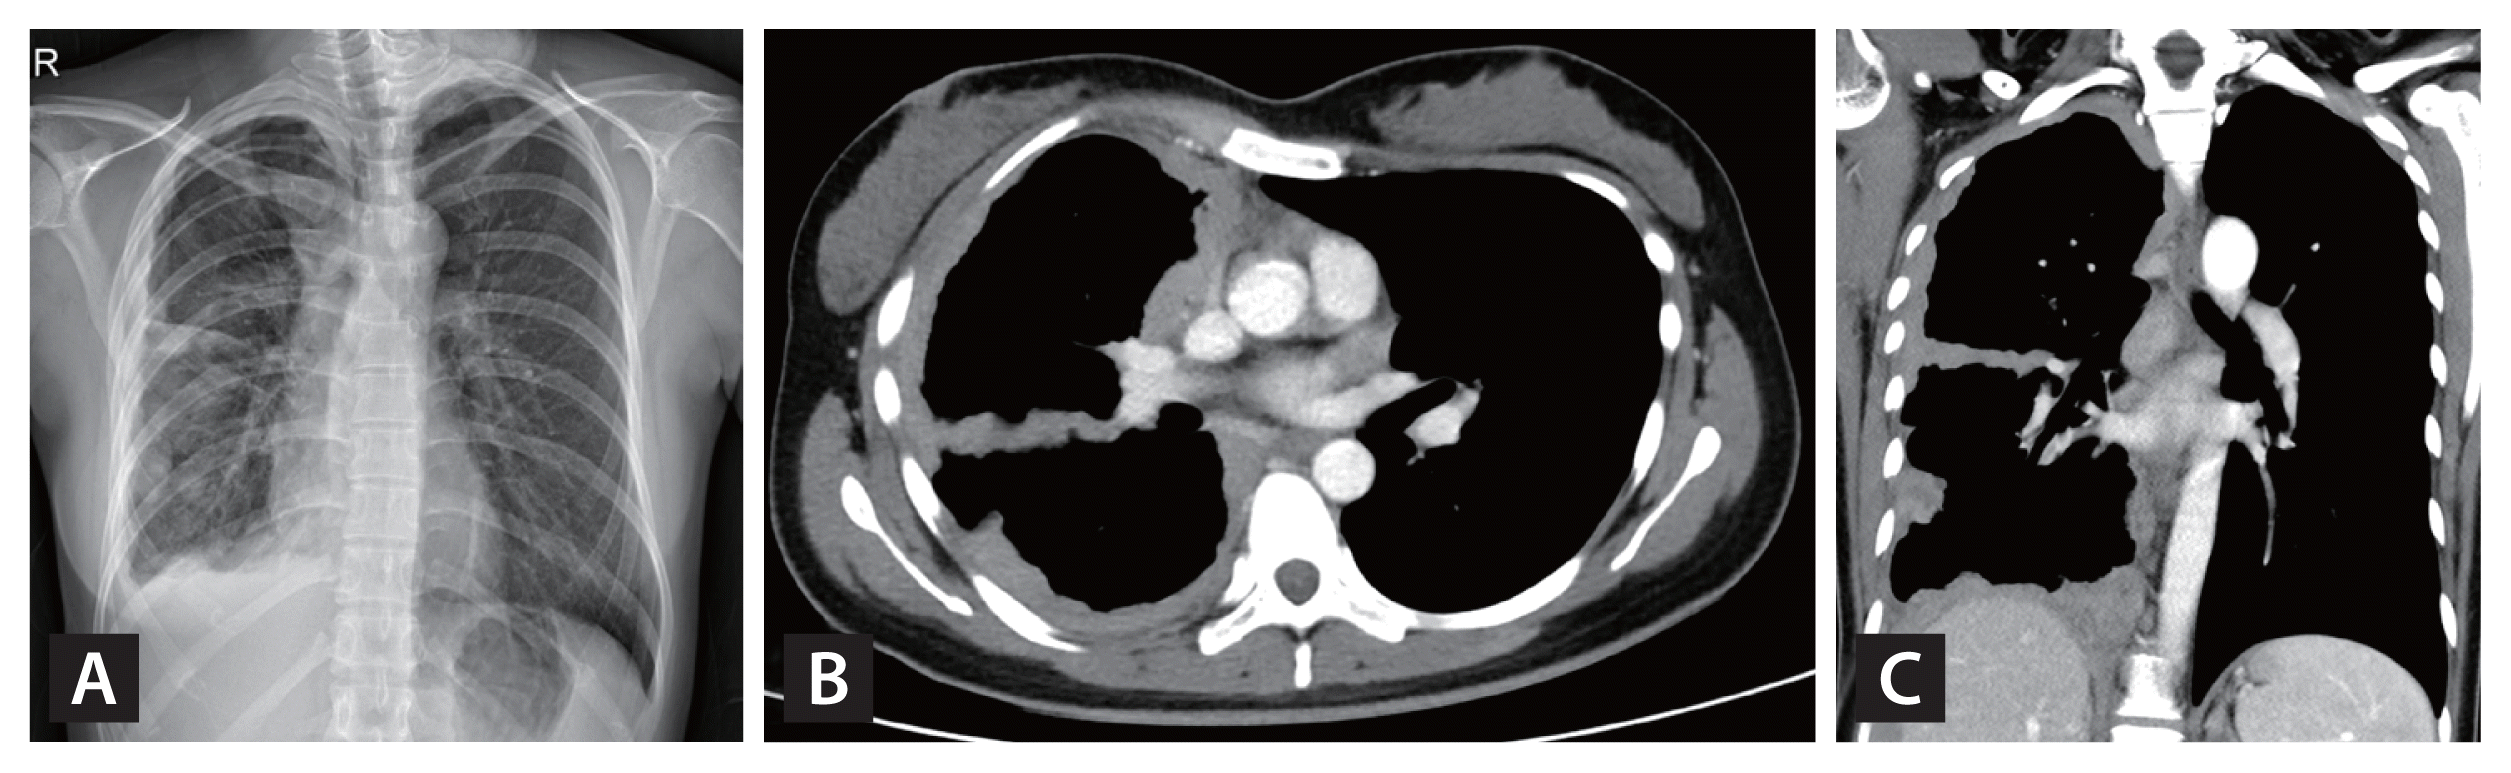

A 26-year-old woman presented to our hospital f or radiologically abnormal pleural lesions at a health check-up. She was asymptomatic with normal laboratory findings. A chest X-ray showed diffuse nodular pleural thickening in the right hemithorax (Fig. 1A). On computed tomography (CT), the extensive pleural thickening involved interlobar fissures and the diaphragmatic pleura, combined with multiple lymphadenopathies in the mediastinum and the anterior diaphragmatic area (Fig. 1B and 1C). These lesions had increased 18F-fluorodeoxyglucose (FDG) uptake on positron emission tomography-computed tomography (PET-CT) (Fig. 2A–2C), suggesting pleural malignancy such as mesothelioma. Chest magnetic resonance imaging (MRI) with enhancement revealed that the pleural lesions showed moderate enhancement after contrast infusion and diffusion restriction on diffusion-weighted images (Fig. 2D and 2E). For a definite diagnosis, video-assisted thoracoscopic pleural biopsy was done. The lesion had chronic granulomatous inflammation with multi-nucleated giant cells with a negative PCR result for Mycobacterium tuberculosis/ non-tuberculous mycobacterium and a few acid-fast bacilli in Ziehl-Neelsen stain. Finally, M. tuberculosis was cultured in bronchial specimens.

Figure 2

Positron emission tomography-computed tomography (PET-CT) and chest magnetic resonance imaging (MRI) of the patient (A–E). On PET-CT, maximum intensity projection image shows increased 18F-fluorodeoxyglucose uptake (maximum standardized uptake value, 21.9) along the nodular right pleural thickening and the enlarged lymph nodes (A, B, C). Diffusion-weighted image (D) and apparent diffusion coefficient map (E) on MRI of the chest with enhancement show diffusion restriction of the circumferential nodular pleural thickening in the right hemithorax.